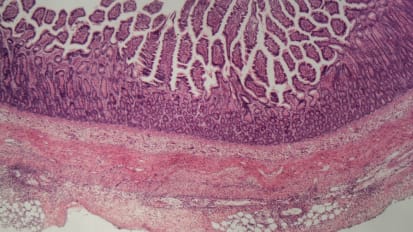

3D Tissue Models Offer Window into How Gut Cells Fight Infection

Nicholas Zachos and his team are the first to cultivate a primary human macrophage-enteroid system, which allows researchers to see, in real time, how the gut fights against infection.